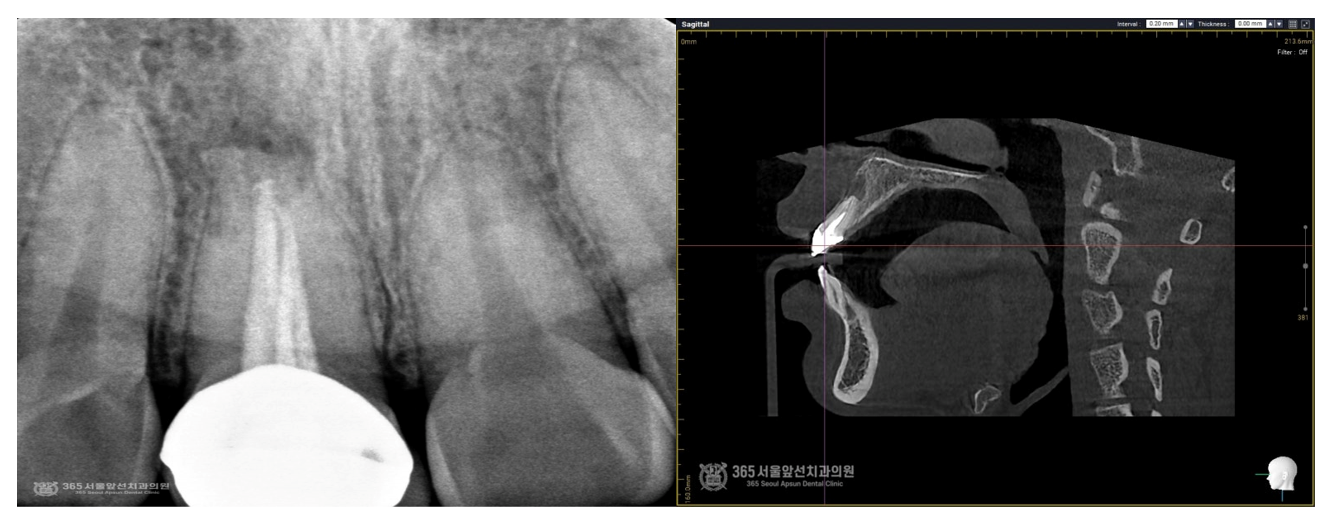

촬영일시 : 2024.09.13 정밀한 검사를 위해 작은 엑스레이 및 3차원 CT촬영을 진행 했는데요. 엑스레이 소견상으로도 뿌리 끝에 까맣게 염증주머니가 확연히 보이고, 3차원 CT 영상으로도 치아 뿌리 끝에 까맣게 염증주머니가 관찰되며, 잇몸뼈를 뚫고 입술 쪽으로 염증이 퍼져있는 모습이 보입니다.